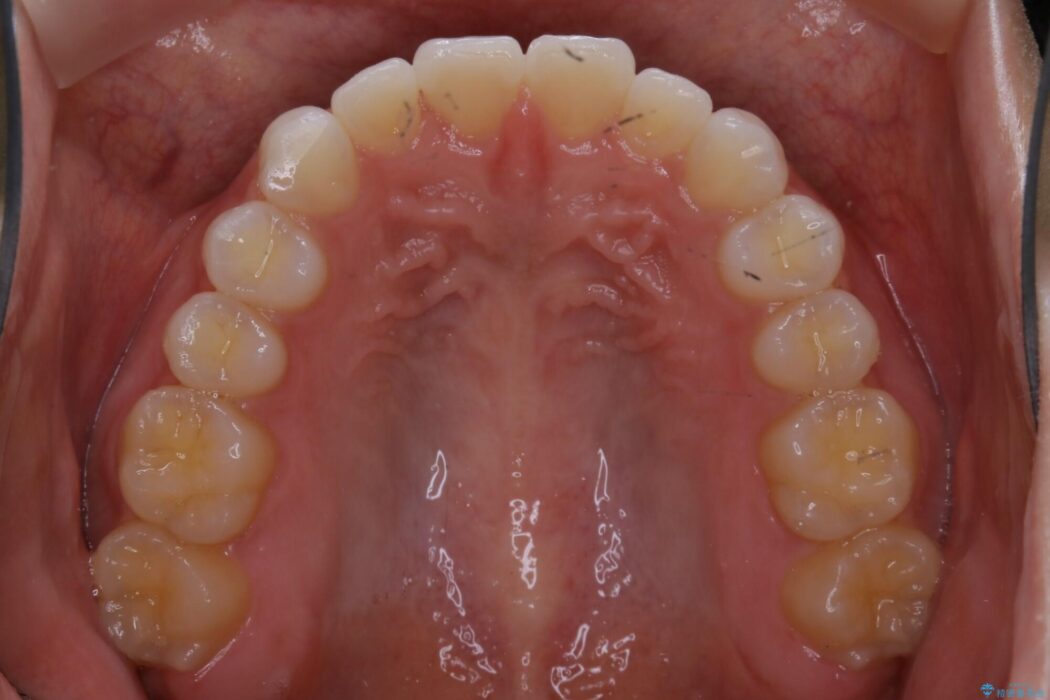

上下前歯のねじれなどで生じている歯列のガタつきをなおしたいとのことで来院されました。

精密検査をしたところ、奥歯に大きな問題がないため移動はほとんど必要がなく、また主訴であるガタつきの改善に必要なスペースも少量であったため、インビザラインのライトパッケージの治療をご提案しました。